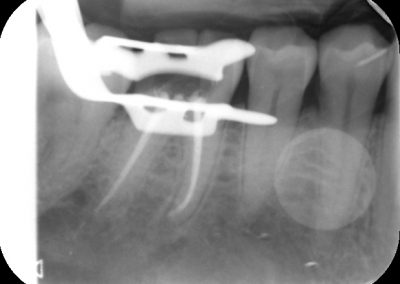

An access cavity is placed on the surface where the patient bites, to reach the root canals of the tooth. Once all the canals are identified, small files are used to remove the infected pulp.

Files of different sizes are used to eliminate bacteria and infection and to shape the canals. The canals are disinfected thoroughly with irrigants and later the canals will be sealed in 3 dimensions with a special medicament called gutta-percha to prevent reinfection of the tooth and the access cavity will be sealed with a temporary filling.